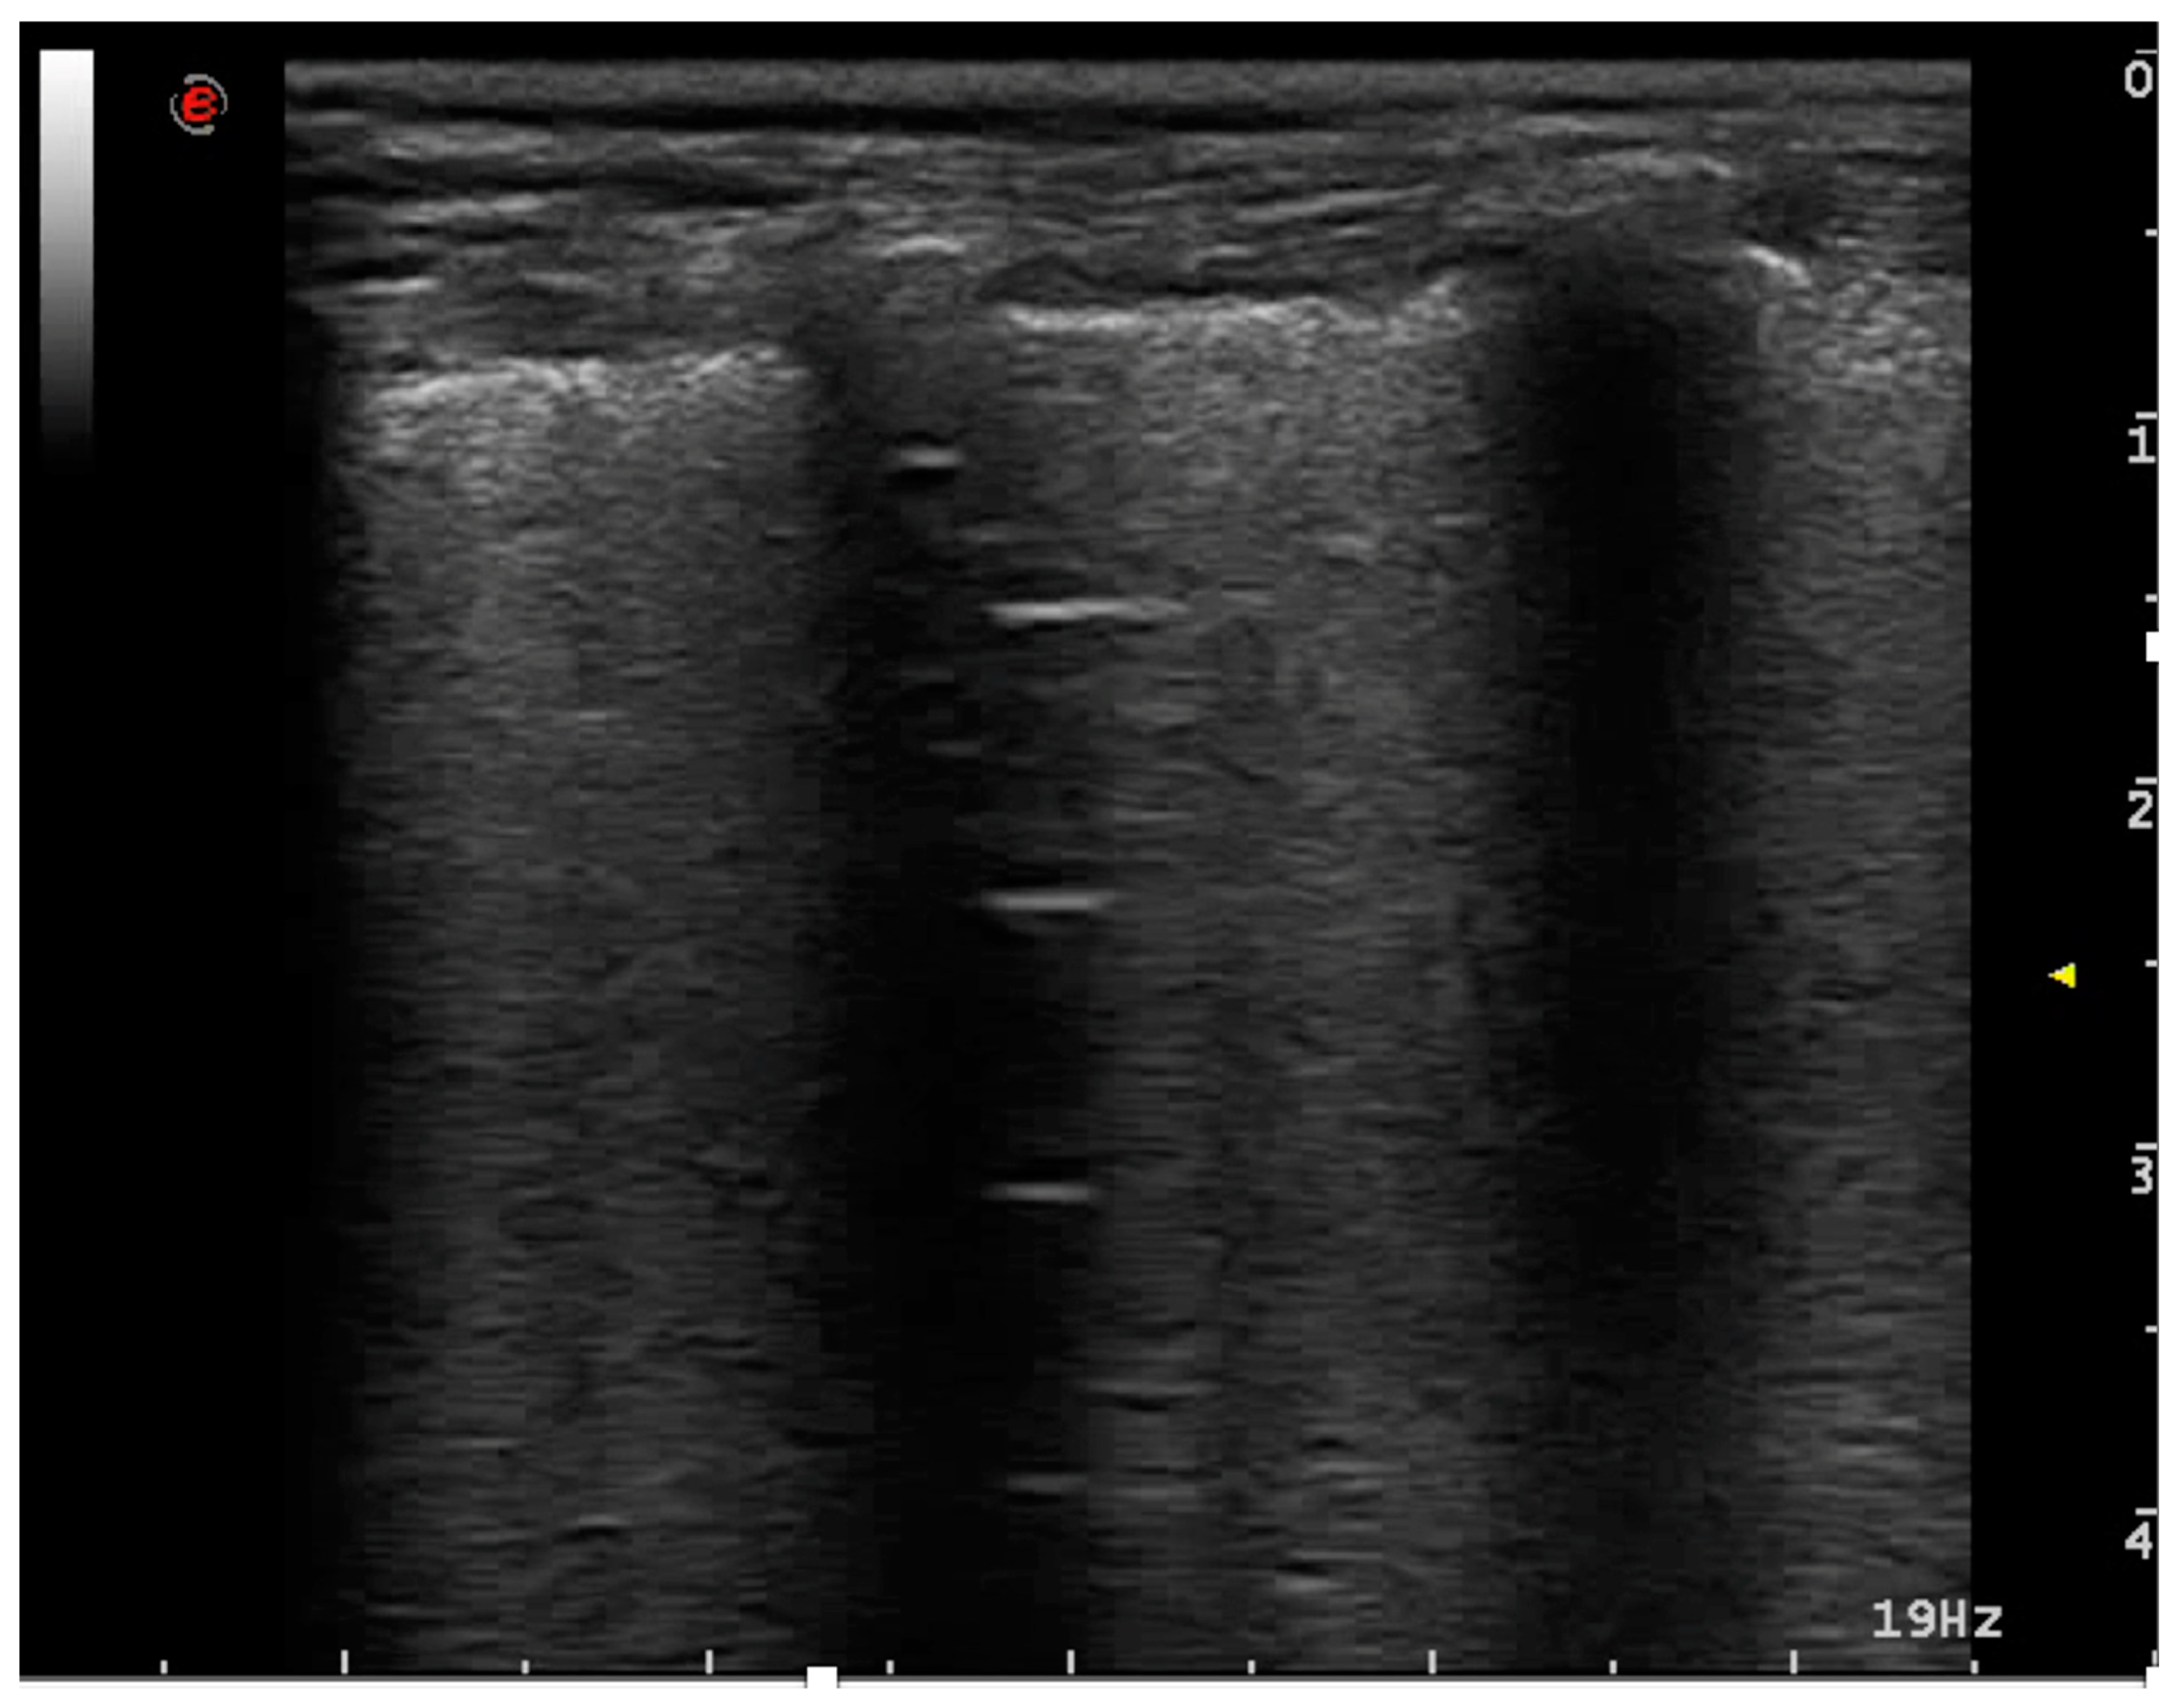

3.2.1. Pneumonia and Atelectasis